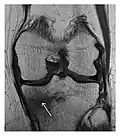

Figure 1: A 56-year-old woman presenting with left knee pain after a fall. (a) Initial anteroposterior radiograph was considered normal, however, subtle cortical disruption of the anterior rim of the medial tibial plateau, medial to the tibial spine, is noted (arrow). (b) Coronal T1-weighted MRI confirms the cortical disruption (arrow) and shows extensive fracture through the proximal tibia. (c) Coronal proton density-weighted image with fat saturation shows extensive edema in the subchondral bone. Note also hypersignal adjacent to the medial collateral ligament corresponding to a grade I sprain (arrowheads).[1]